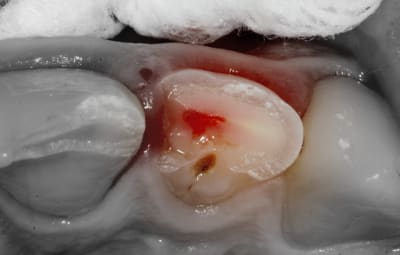

Sur la photo4, celle apres la pulpo partielle je suppose, as tu eu une hémostase naturelle ? As tu directement posé le MTA ? La pulpe semble assez "rouge foncé"

- L'hémostase est faite avec un coton stérile (des boulettes de coton dans un sachet passé à l'autoclave).

Une pulpotomie partielle est réalisée afin d'éliminer le tissu le plus contaminé. De la Biodentine est utilisée ; son avantage par rapport au MTA est de ne pas noircir. Du CaOH aurait un taux de succès moindre.